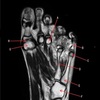

3

4

5

Perfectly

13

Q

What is letter C?

A

HEAD OF HUMERUS

How well did you know this?

1

Not at all

2